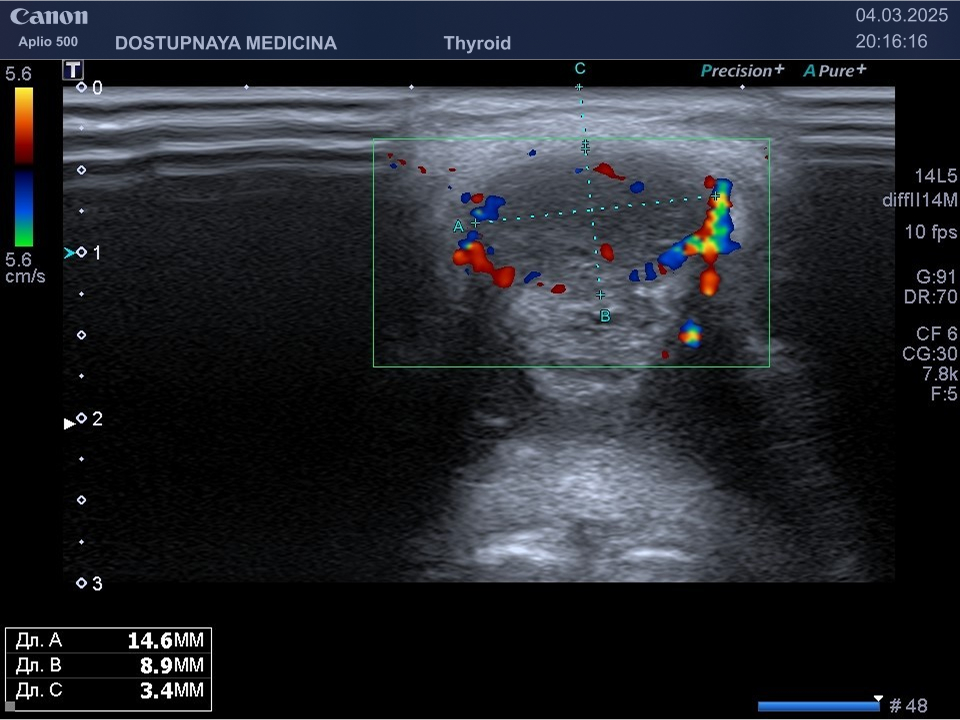

При ультразвуковом исследовании липосаркома чаще всего выглядит, как гипоэхогенное образование неправильной овальной формы, обычно с более пониженной эхогенностью (темнее) по сравнению с окружающей её подкожной жировой клетчаткой, с усиленным кровотоком в режиме ЦДК. В описании заключения важно так же отметить прилежит ли близко опухоль к какому-либо кровеносному сосуду или нерву.

Видно, что кровоток в образовании значительно усилен.